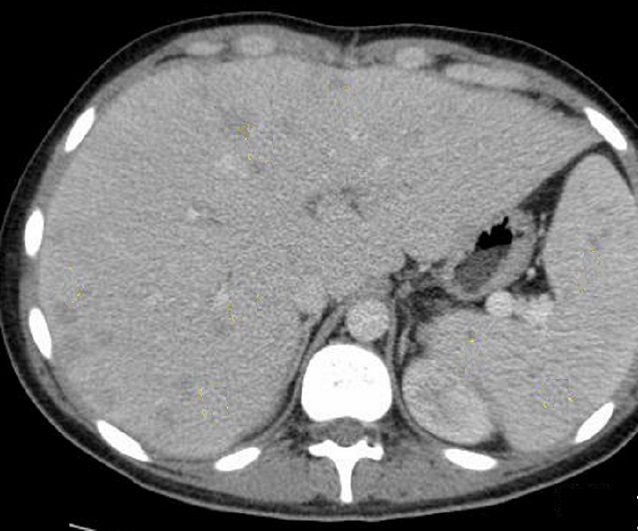

Image TDM

de abces du foie : Aspect TDM de abces du foie est

variable : lesion en apparence peripherique de hyperdensite

et a central hypodense s'observe souvent dans abces amibien . Ce qui peut en presence de

gas ( 20% de gas ) . Aspect en cloisone ou multiple

loculaire , bien definie " cluster sign" peut

se retrouve dans l'abces a pyogenes. En cas de TDM

plus de contrast intraveineuse , image de double de cible "double

target sign" peut en voyait .

Aspect radiologique TDM d'une abces

a pyogenes multi loculaire du foie en realisee sous forme de

grappe "cluster sign " . |